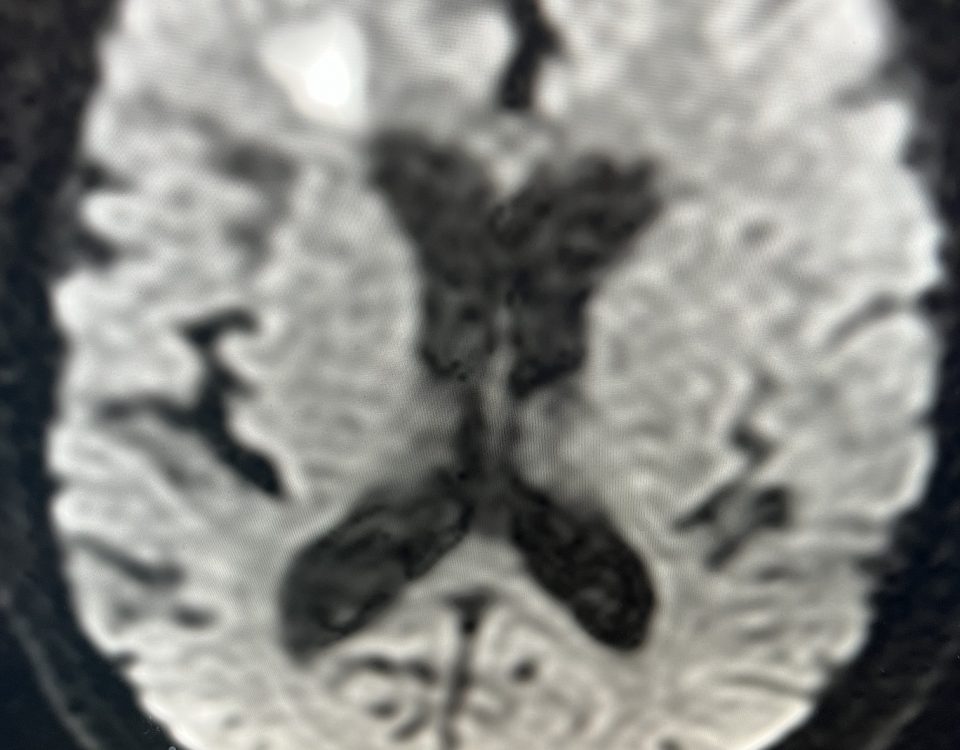

Case Presentation: A woman in her 80s developed mild dizziness and headache following incidental trauma working in her garage one day. She presented several weeks later […]